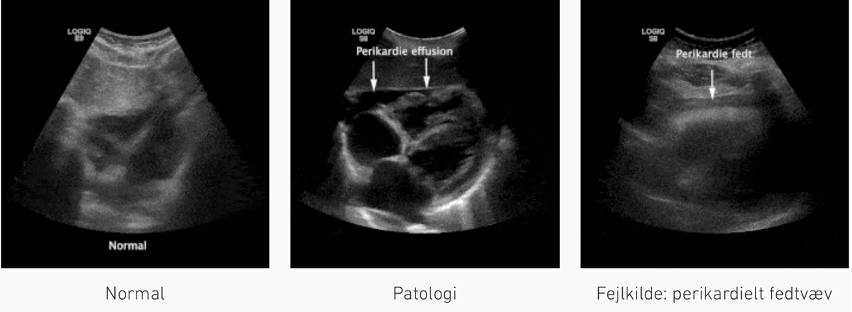

Zone 3 (Subxifoid position): 1

1: perikardieansamling